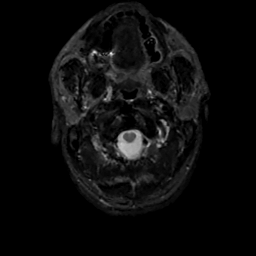

MR Study #12, May 12, 1991 -- Slice #0